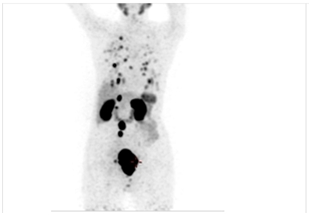

Pre-therapy PSMA Scan with disease in Prostate Gland, Retroperitoneal Lymph Nodes & Lungs (seen as black spots)

After one cycle of Ac225 PSMA Therapy, the patient had a remarkable reduction in the active tumour from the lungs (black spots in the image on the left), Retroperitoneal Lymph Nodes, as well as shrinkage of tumour in the Prostate Gland.